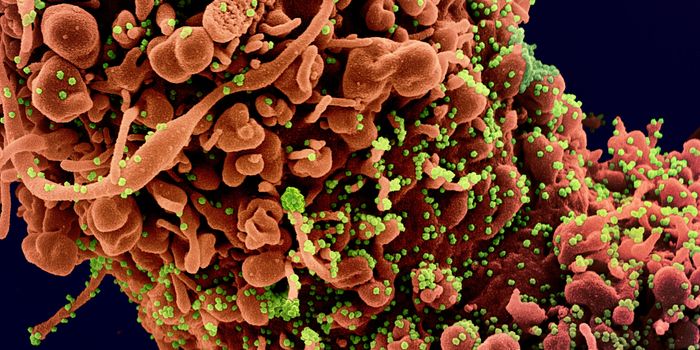

APR 04, 2022Cell & Molecular BiologyAbout 1.5 million new HIV infections are thought to have occurred last year, and while COVID-19 has dominated concerns a ...